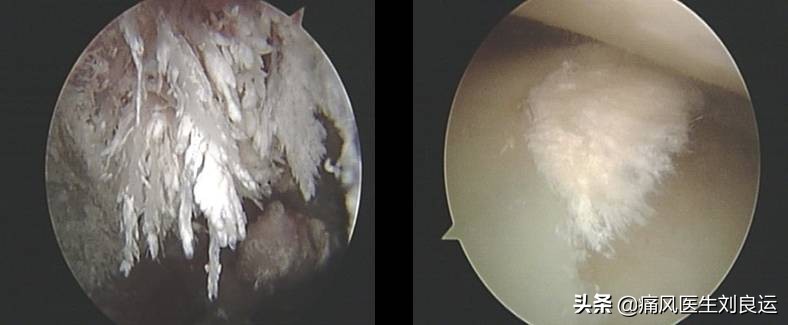

针刀镜下关节内散在尿酸盐结晶

针刀镜下痛风石沉积关节的尿酸盐结晶

针刀镜下痛风石治疗